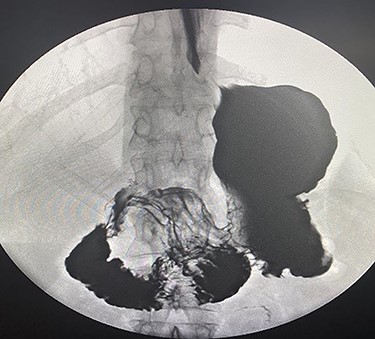

A 35-years-old female, 9 months post-endoscopic gastroplasty presented to the emergency department complaining of epigastric abdominal pain for 5 days, the pain is radiating to the umbilicus associated with nausea and vomiting. On general examination, she is vitally stable with HR 88 B/min, BP 116/66 and temperature 36.9°C, the abdominal examination showed epigastric and tenderness. On abdomen CAT scan, she had partial small bowel obstruction with adhesive band originating from the stomach (Fig. 1). Barium meal showed dilatation of the second part of duodenum due to band like structure (Fig. 2). The patient admitted to the hospital with a diagnosis of small bowel obstruction and kept NPO; Nil Per Os, on IV fluids and nasogastric tube drainage.

Barium meal showed dilatation of the second part of duodenum due to band like structure.